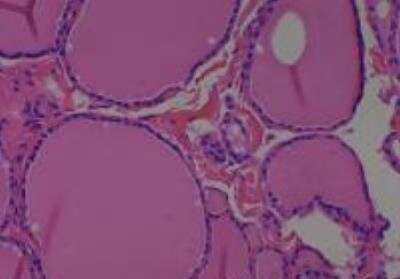

Hematoxylin & Eosin Stain: Human Common Tissue MicroArray (Normal Adjacent) [NBP2-30215] - 103. Stomach